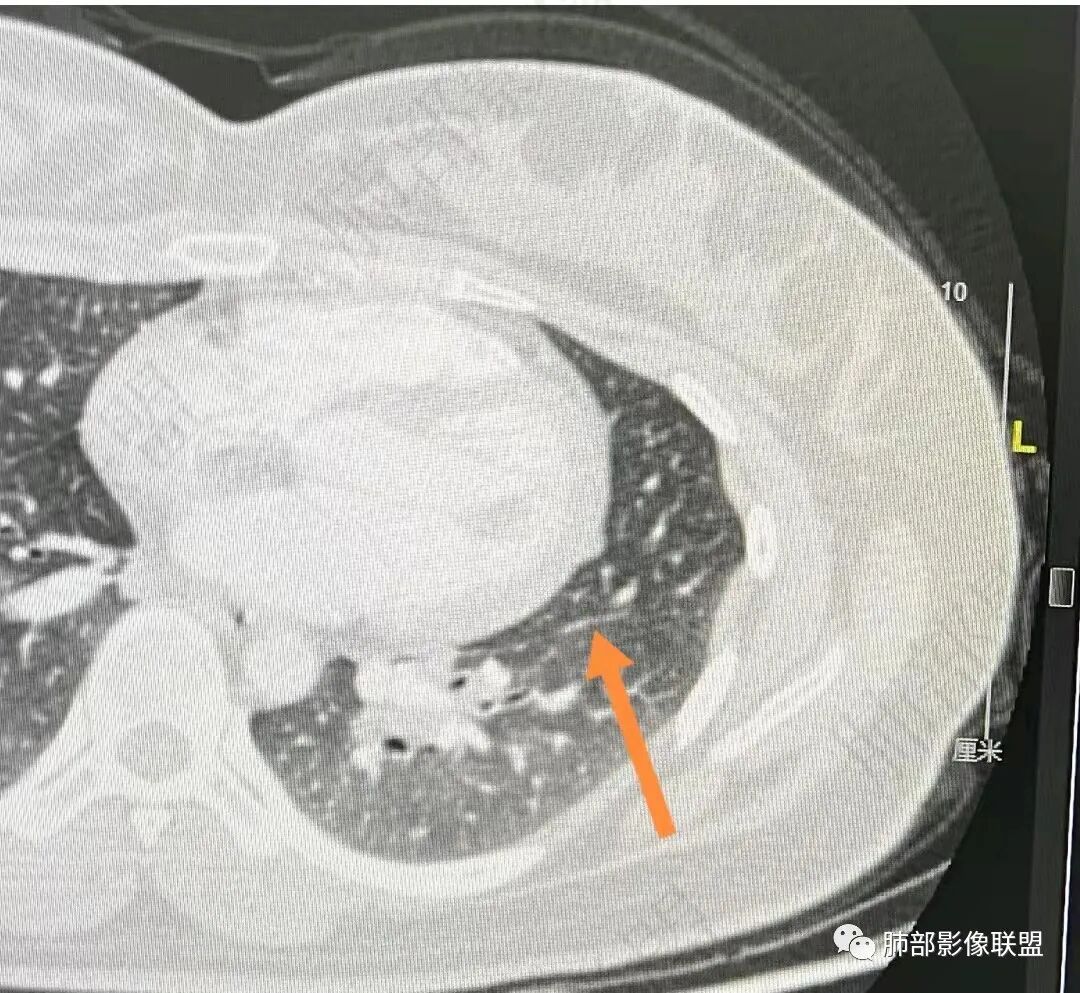

2、影像特点:双肺部分区域小叶间隔增厚并串有微小结节影,叶间裂见微小结节影。纵隔、双肺门多发肿大淋巴结,密度较高,边界清楚,未见坏死及钙化。

3、病例小结:年轻女性,无临床表现。纵隔、双肺门多发淋巴结增大(尤其双肺门淋巴结对称性增大)+叶间裂结节+小叶间隔结节,常规应想到结节病可能。